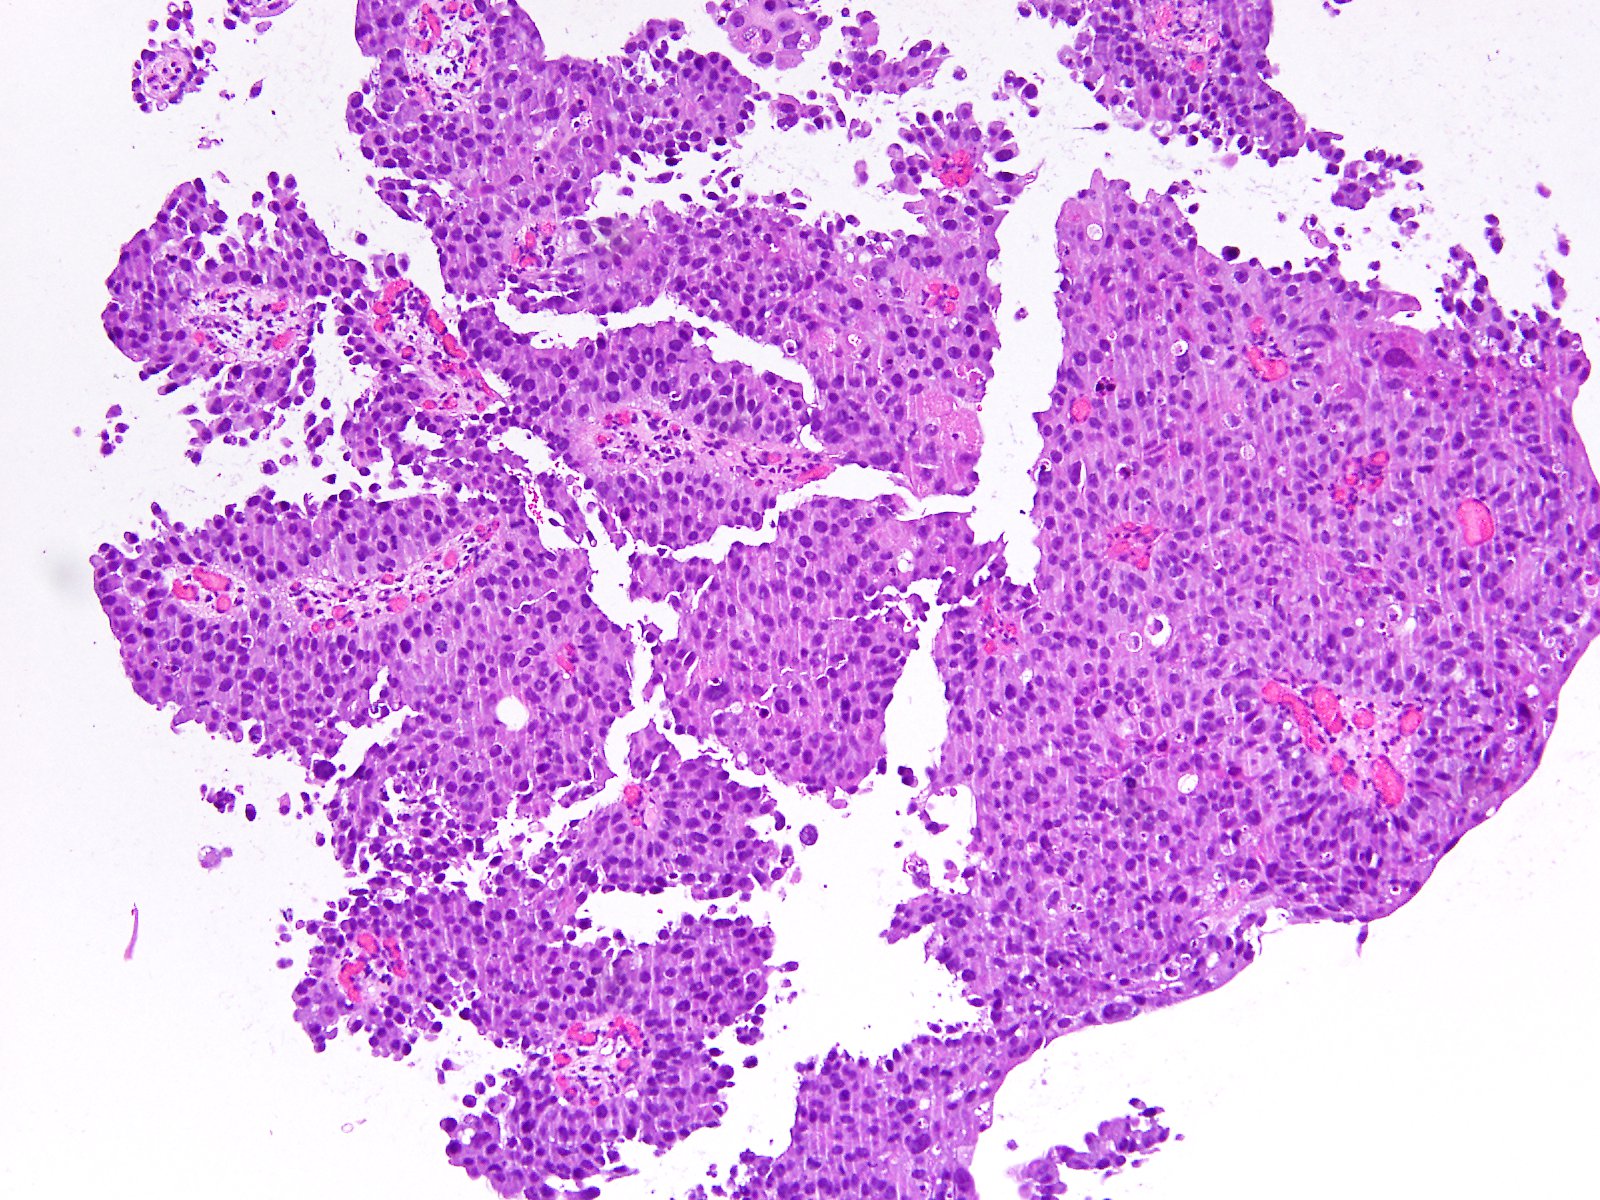

Bladder Papillary Lesions

Case ID: 363